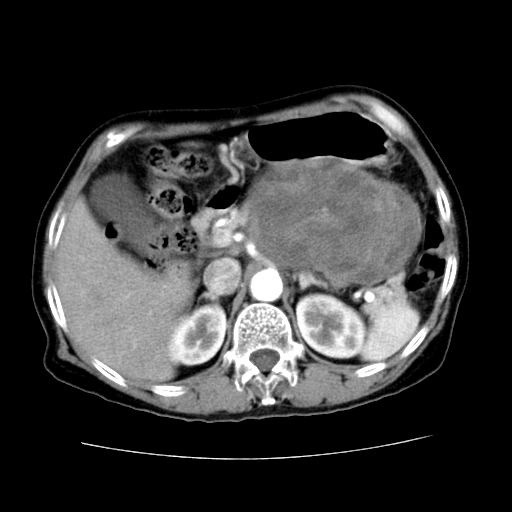

女性,72岁。

主诉中上腹部疼痛不适1年余。

该例有几个特点需注意:

1.肿瘤大而边界清

2.内部有钙化

3.强化时间较长

4.这么大的肿瘤对周围的血管无侵犯

以上几条均与胰腺癌不符

故考虑:胰岛细胞癌

2、手术所见:打开腹腔发现胃与胰腺体尾部可见肿块,大小约10×8×11cm,质硬,不可推动,周围血供丰富。术中诊断:胃肿瘤侵及胰腺体尾部。

1)、胃小弯侧胃肠间质瘤(考虑恶性),瘤体大小13.5×7×6.5cm,上下切缘阴性。

4、这个肿瘤太大了,而且密度不均性强化,从这点我们应该不能单纯诊断胰腺癌,而应想到目前流行的胃肠道间质瘤。这个肿瘤主要发生于胃壁浆膜层,所以显示与胃壁关系不是很紧密,故而大多认为是胰腺癌。